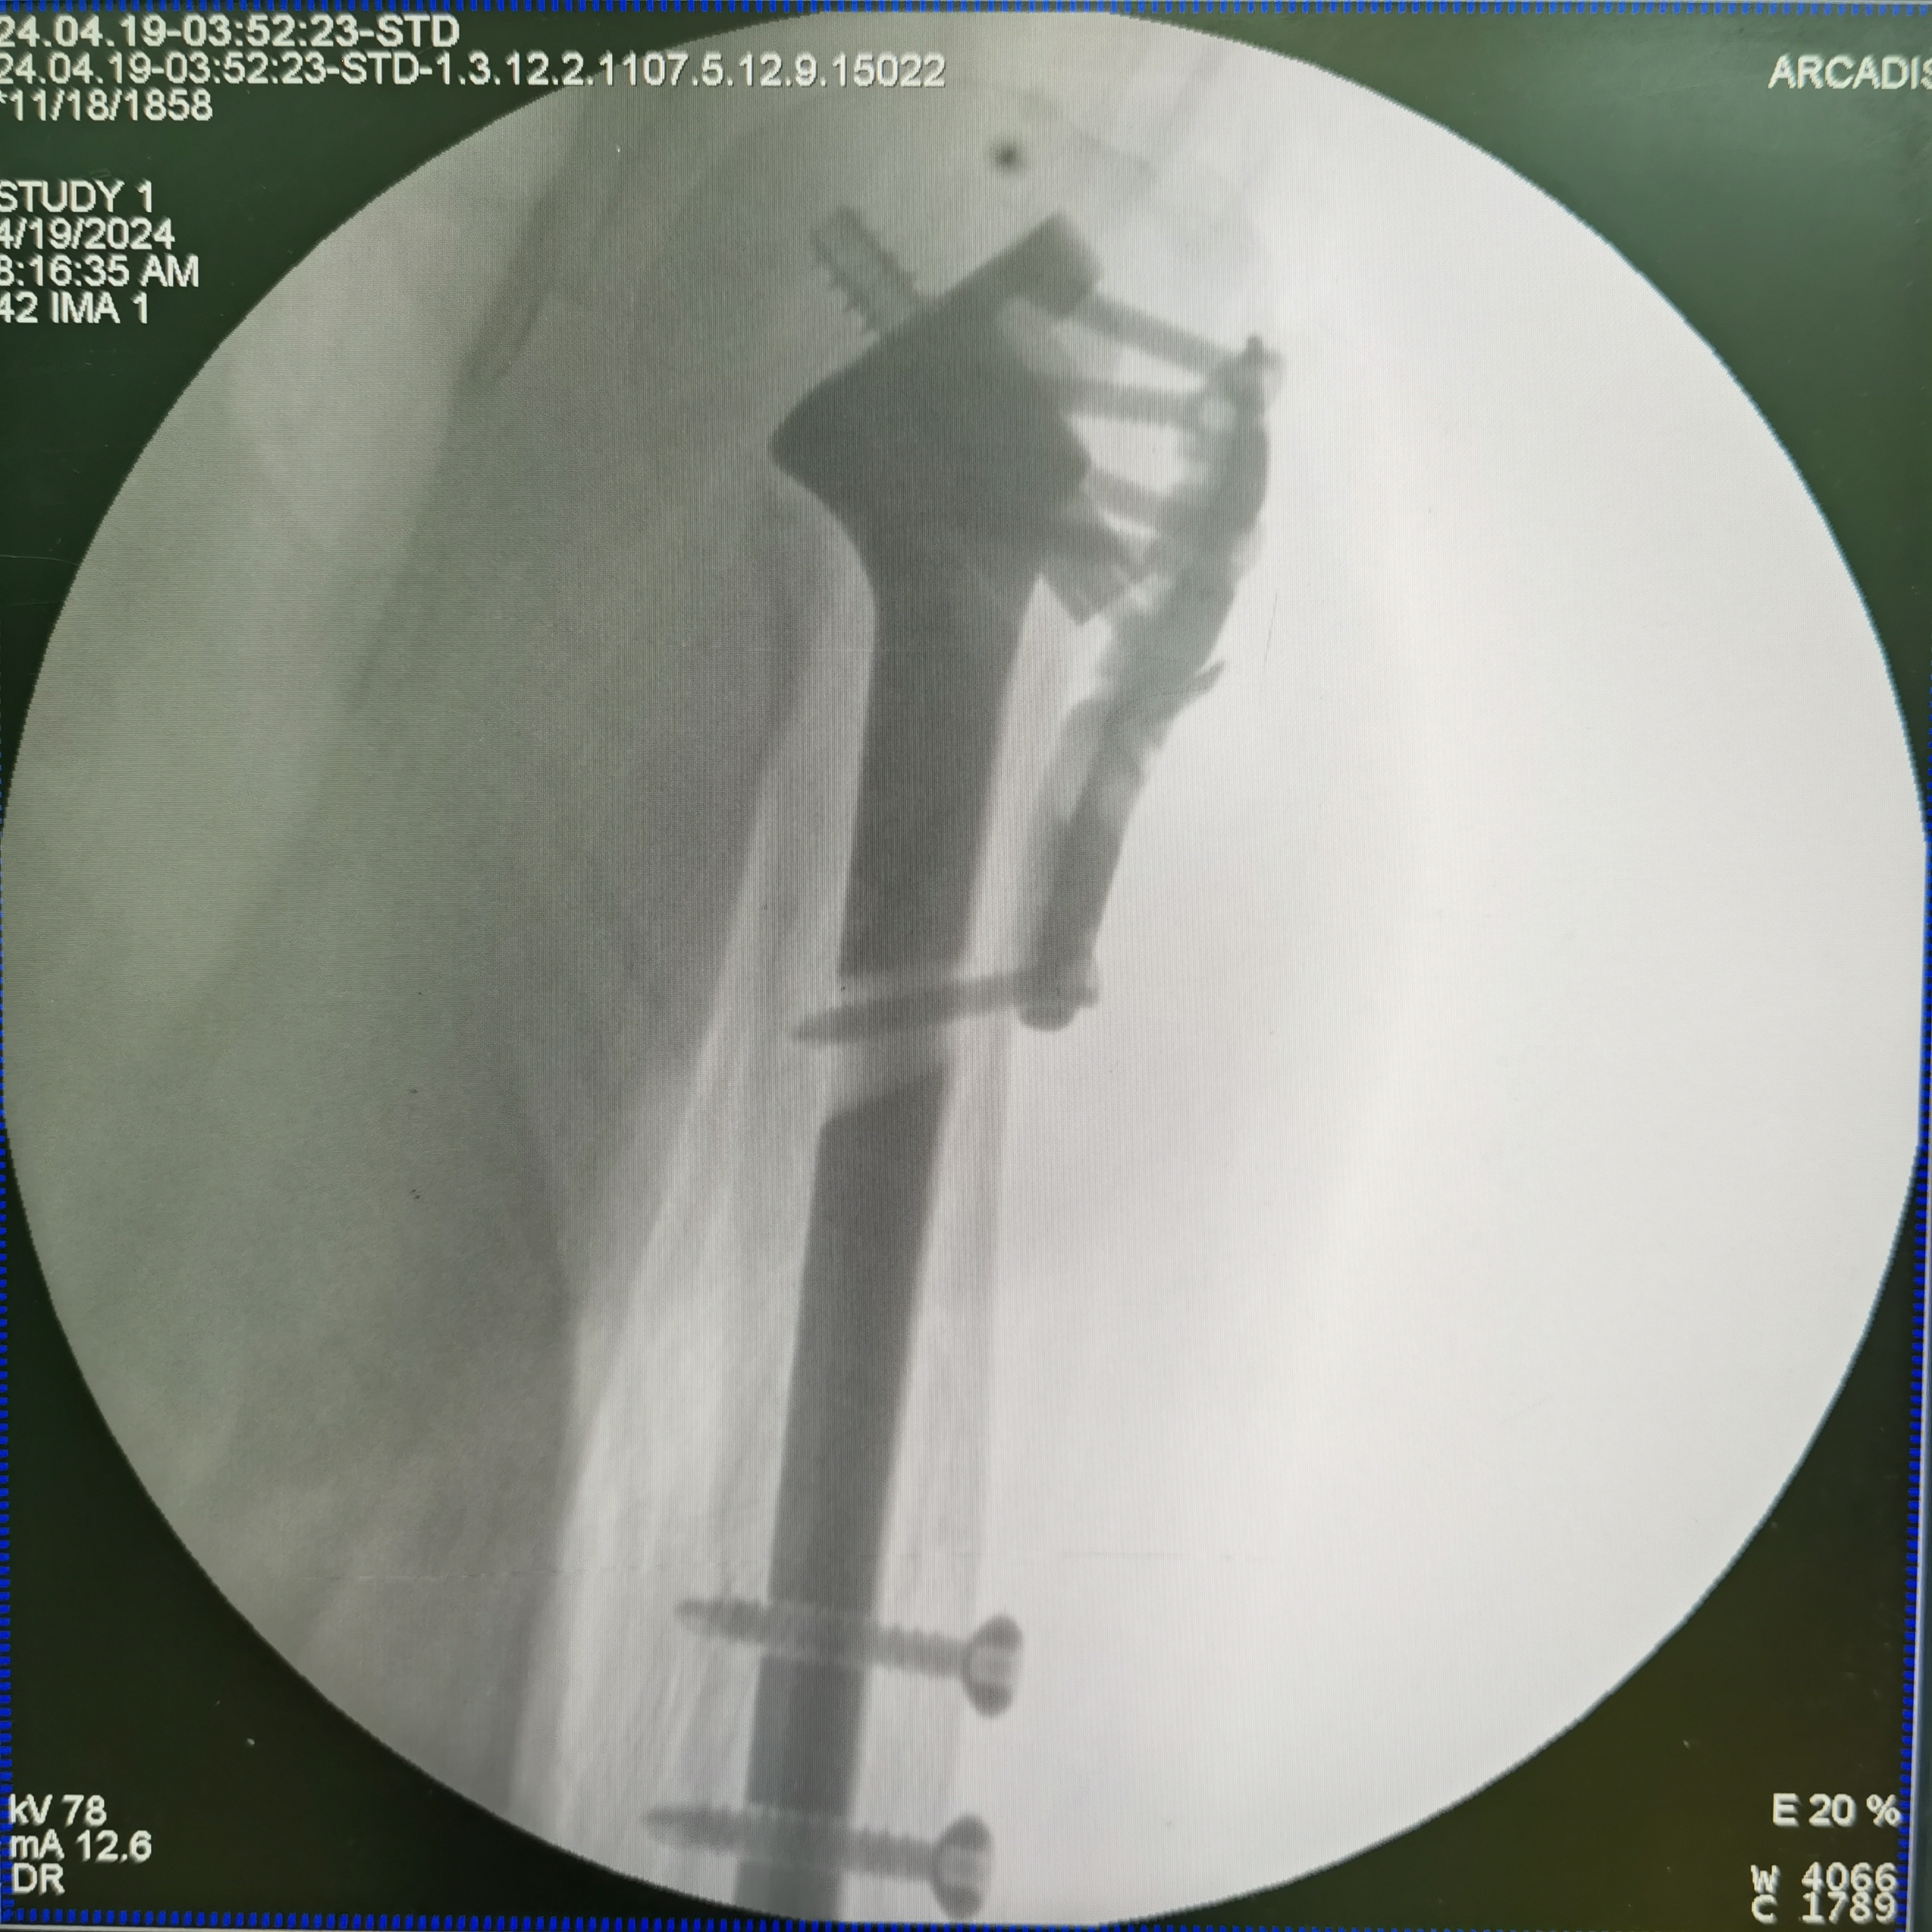

老年肱骨近端骨折---解剖髓內(nèi)支撐Endosteal anatomic support nail

老年女性,65歲,肱骨近端骨折,嚴(yán)重移位,骨質(zhì)疏松。如何使用解剖髓內(nèi)支撐技術(shù)獲得穩(wěn)定,允許早期功能鍛煉。視頻顯示解剖髓內(nèi)支撐治療老年肱骨近端骨折嚴(yán)重錯位,有效恢復(fù)肱骨近端解剖結(jié)構(gòu)。